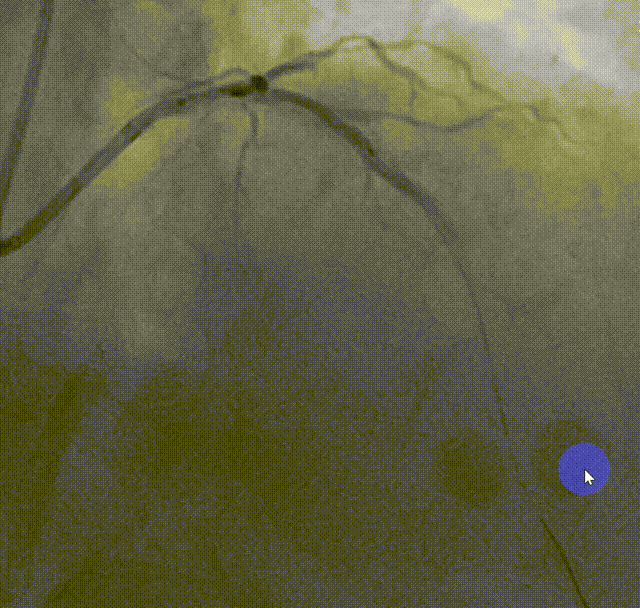

LM-LAD支架释放后造影